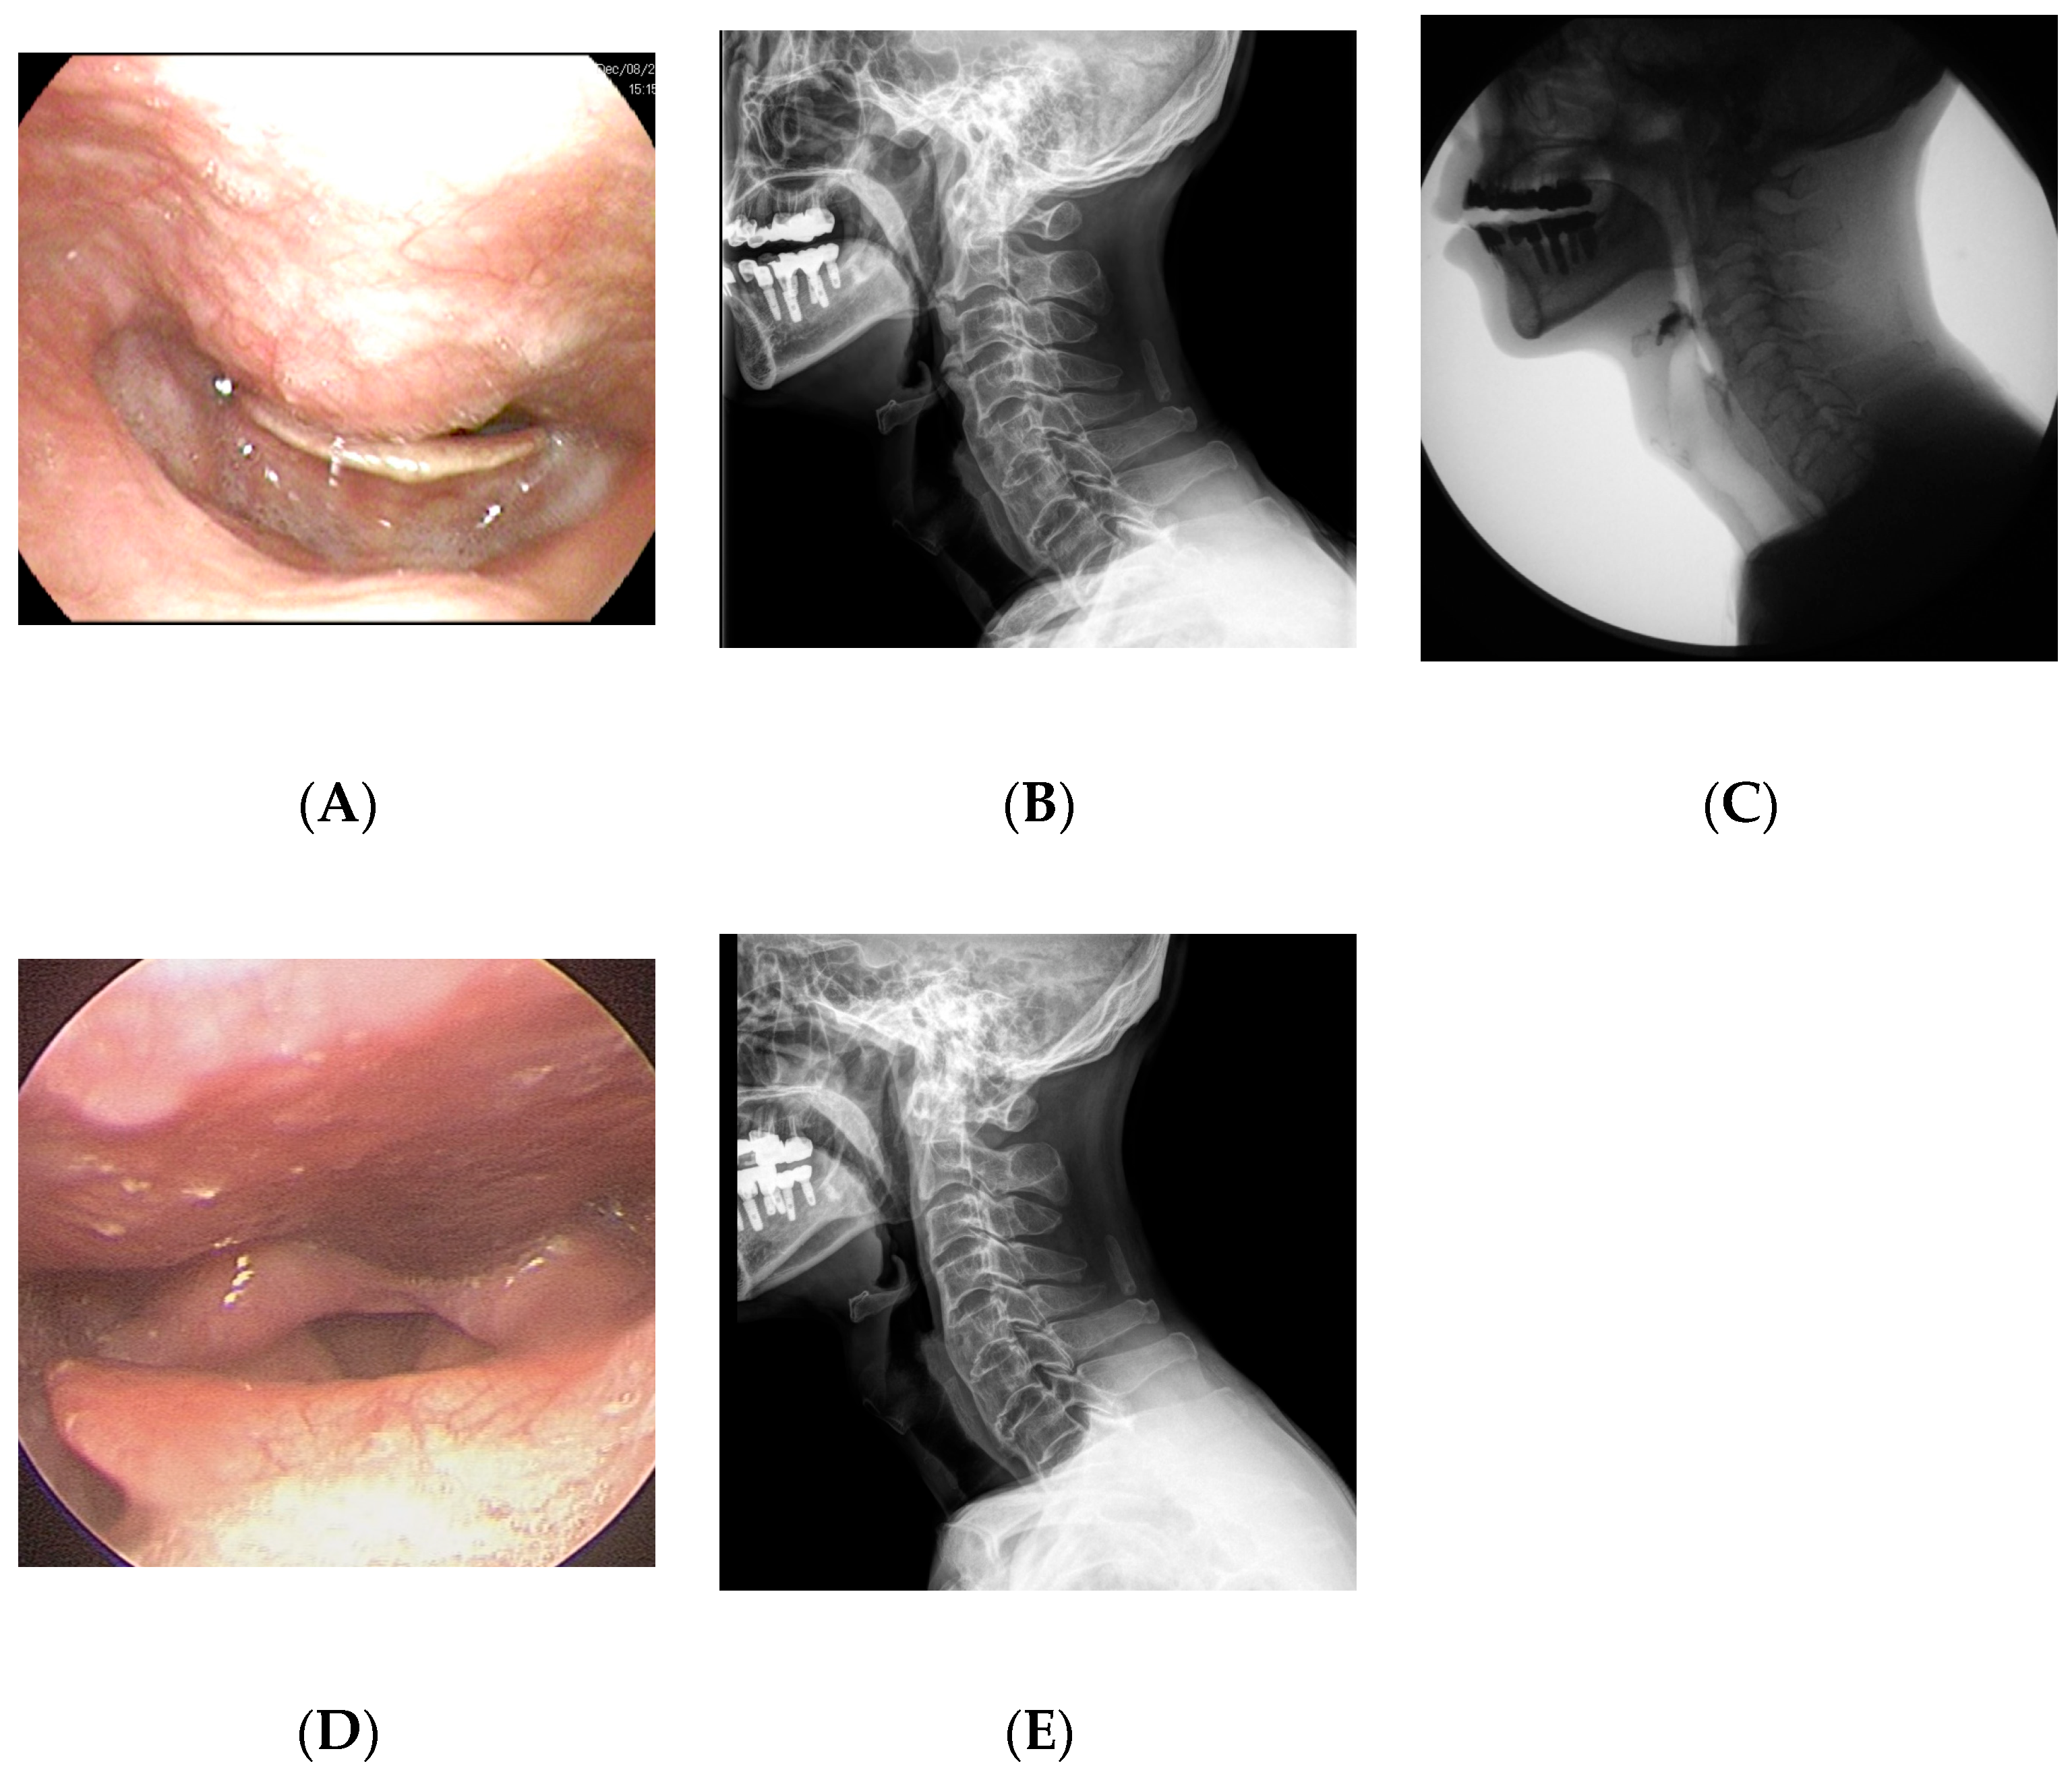

2.1. Case 1

2.2. Case 2